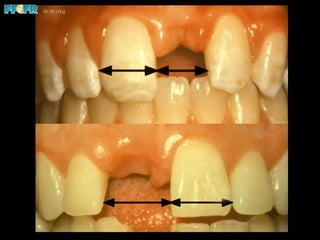

Effect of Bonding Area

•  The area available for bonding affects success

Thayer, 1993

Priest, 1995

Ferrari, 1998

• The mean area of debonded retainers was 38

mm2 compared to retainers that did not debond

(45 mm2)

• Age and gingival position affected the area

available for bonding

Prosthesis failure due

to minimal coverage

More appropriate area

covered